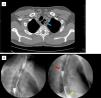

A) Axial CT view: The cervical esophagus is dilated, with a double lumen in its interior that does not communicate with the trachea (blue arrow). B) Esophagogastric transit. Oral contrast medium is shown passing through the esophagus to the esophagogastric junction (yellow star) and into the second esophageal lumen, where it remained static (red arrow).